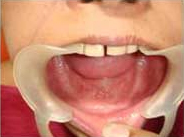

After Placement of Prosthesis

Single Tooth Implant